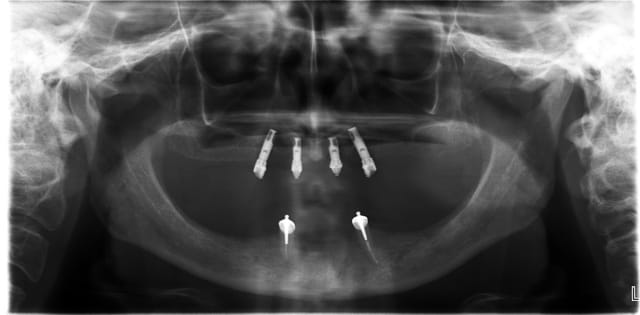

j'ai recupéré ce joli sourire, je pense que c'est du MK2, pouvez vous me le confirmer mais surtout , comment on retire ces cônes de protection, et que commander comme accastillage pour la suite.

c'est du Nobel...mk2 mk3....peu importe...c'est le même hexagone externe...

ces "cônes" de protection....et bien c'est des multiunits angulés....il devait y avoir une prothèse là dessus ou alors un capuchon plastique transvissé....

si tu veux démonter les multiunits, il te faudra retirer le composite qui bouche le puits de vissage...(attention à la tête de vis...)